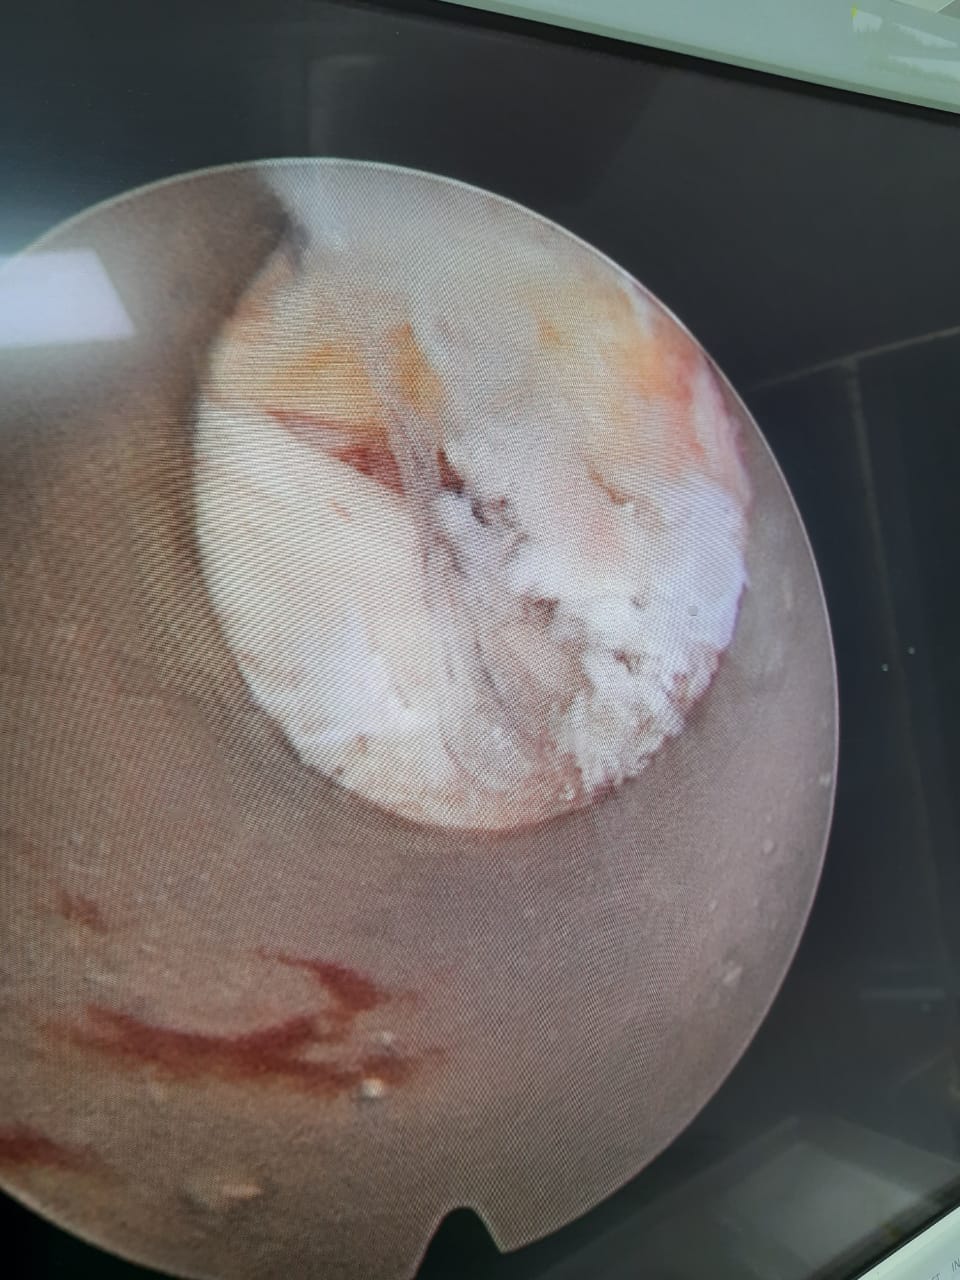

Here are some pics of our first case